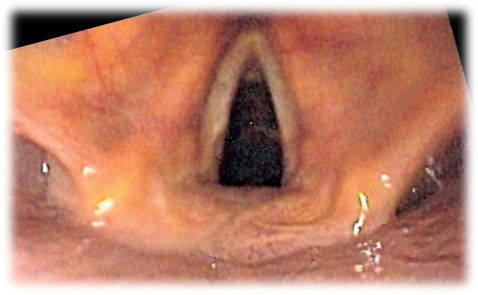

To grow bioengineered mucosa, the researchers started with vocal fold cells harvested from several patients (and one cadaver) who had their larynxes removed. The researchers placed these cells in a special growing solution to make them grow, along with a 3D scaffold like those used to grow the tissue used for skin grafts. After 14 days, the structure and proteins synthetic tissue looked real human tissue, complete with structural proteins not found when the mucosa cells were cultured on their own. See real human vocal cords below for an example of how the synthetic ones worked:

In spite of these many challenges, the researchers are confident that this first study is a great first step to bringing vocal fold tissue repair to the millions of people in need. “We believe this tissue is a promising therapeutic candidate that has the potential to restore vocal function to patients that have lost their voice,” said Matthew Brown, one of the study authors, in a press conference. Check out video of a real set of human vocal cords (not the synthetic ones) in action below: